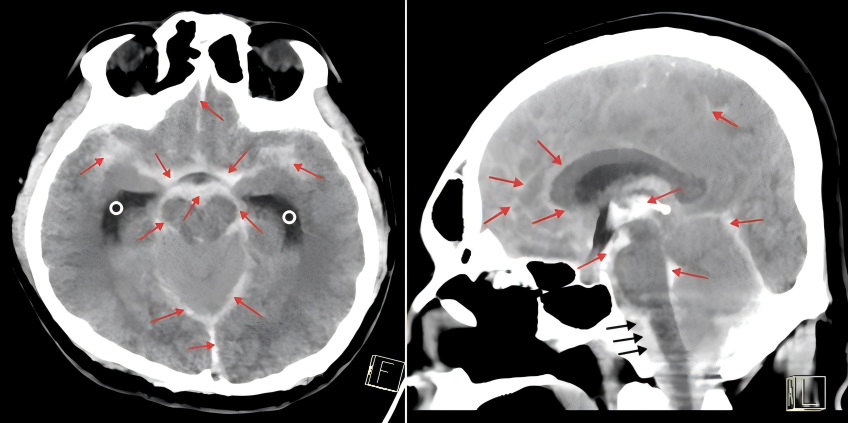

不能等,更不能退!团队果断决定——在呼吸机支持、持续用药和严密监护下“边抢救、边检查”。 头部CT迅速完成,结果令人揪心:蛛网膜下腔出血,合并脑积水,元凶直指死亡率极高的“椎动脉夹层动脉瘤”。